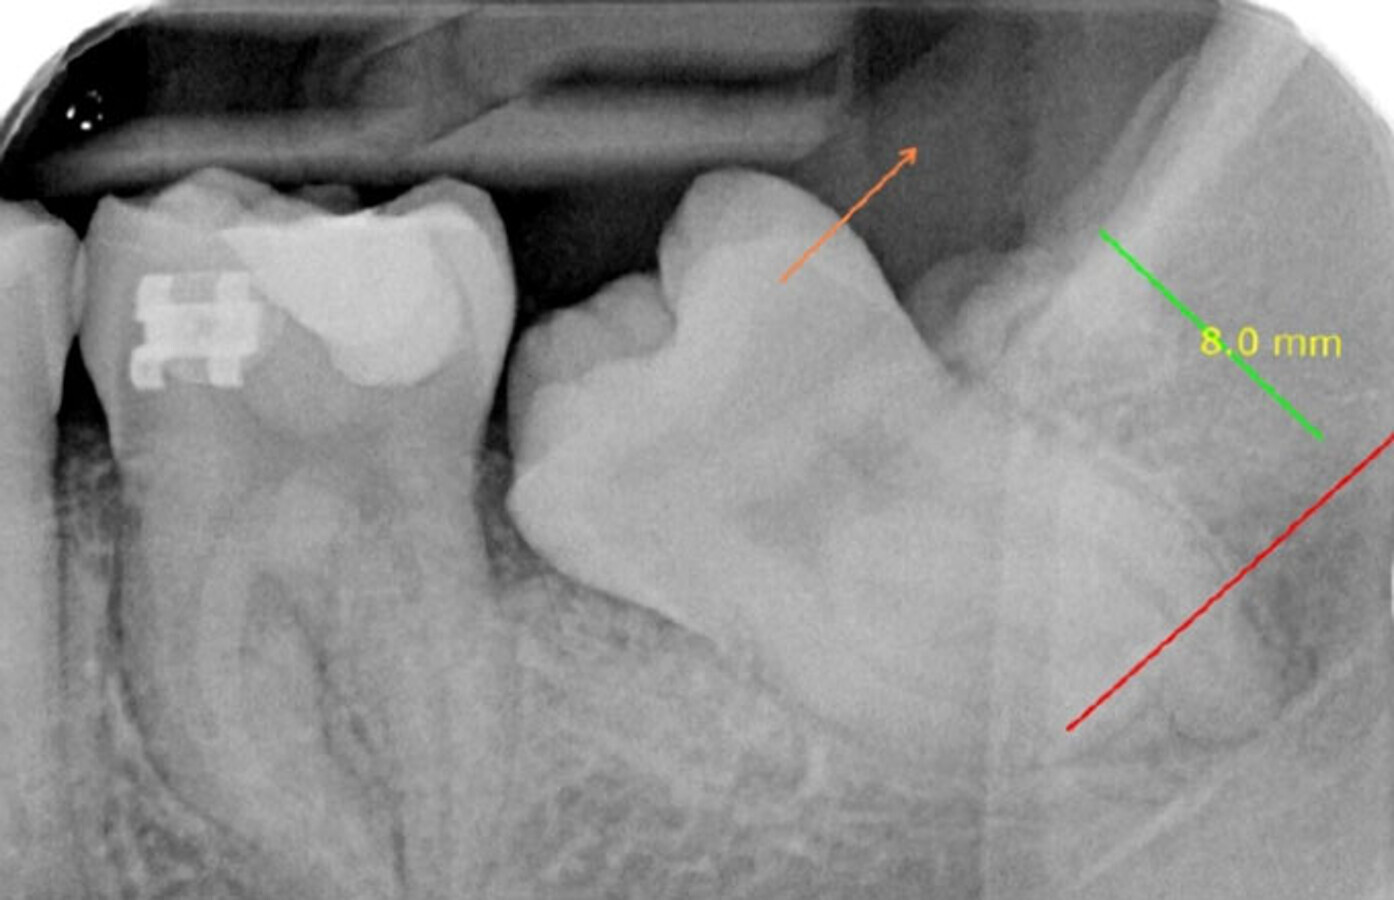

Molar 36 y 37 impactado horizontal.

El autor presenta un caso de un segundo y tercer molar inferior enclavados, “diente retenido que ha perforado el techo óseo, con apertura del saco pericoronario o no, y que puede hacer su aparición en la boca o mantenerse submucoso”, y su tratamiento ortodóntico-quirúrgico.

Los terceros molares inferiores retenidos constituyen aproximadamente un 35% de las retenciones dentarias. Sin embargo, los segundos molares inferiores retenidos sólo se encuentran en un 0,5% de las inclusiones.

Detalle de ortopantomografía.

Estudio de ortopantomografía